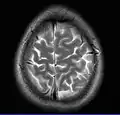

Normal axial T2-weighted MR image of the brain